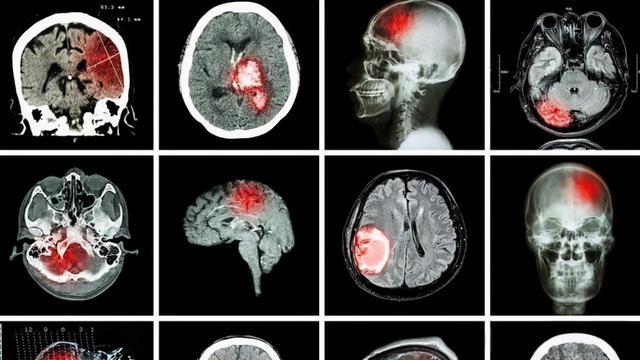

脑梗塞严重威胁人类健康的疾病!

它犹如隐藏在暗处的恶魔,随时可能对人们的身体和生活造成巨大的破坏。脑梗塞,主要是由于脑部血液供应障碍,缺血、缺氧所导致的局限性脑组织的缺血性坏死或软化。一旦供应脑部血液的血管,如颈动脉或脑内动脉发生堵塞,就会引发一系列严重的连锁反应。